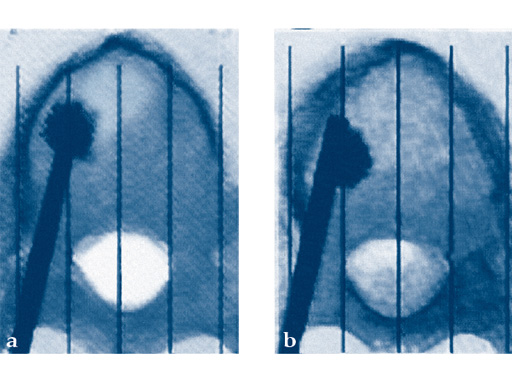

The vertebral body stent (VBS) system is a minimally invasive, percutaneous, reconstructive treatment for vertebral body fractures. The VBS system is intended for the reduction of painful vertebral compression fractures and/or creation of a void in cancellous bone in the spine for the treatment of levels ranging from T5-L5. It is intended to be used in combination with a legally marketed polymethylmethacrylate (PMMA)-based bone cement adequately indicated for use in vertebroplasty or kyphoplasty procedures.

Vertebral Body Stenting (VBS) System w/Balloon (VBB)